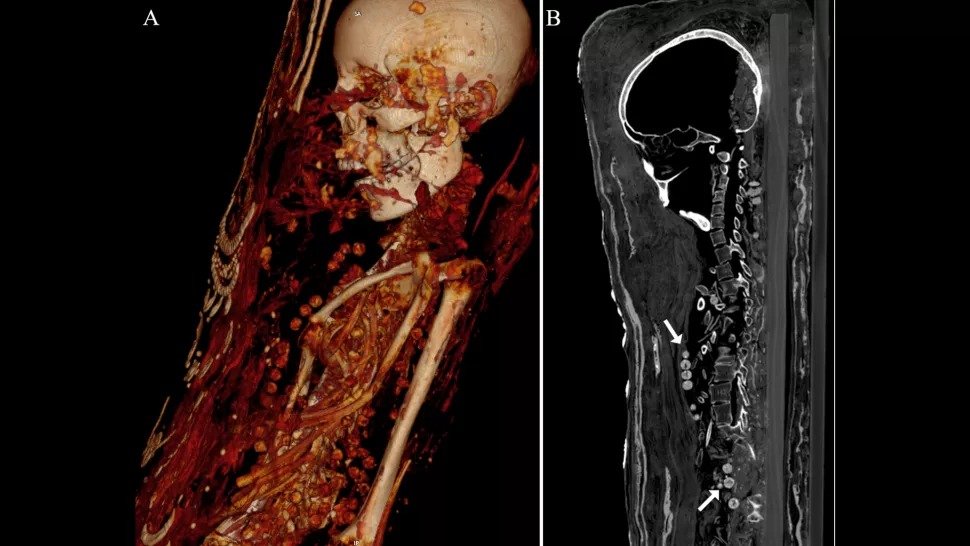

Le scansioni TC (tomografia computerizzata) mostrano che una delle tre mummie rivestite di gesso è stata sepolta con organi (anche cervello) e due donne sono state sepolte con bellissime collane, hanno scoperto i ricercatori.

La tomografia computerizzata ha mostrato che le persone mummificate – un uomo, una donna e un'adolescente vivevano nel periodo tardo romano (30 a.C. – 395 d.C.).

Le mummie furono sepolte con manufatti ritenuti utili nell'aldilà, comprese le monete, probabilmente destinate a pagare Caronte, una divinità romana e greca che trasportava le anime attraverso il fiume Stige.

La tomografia computerizzata ha mostrato che l'uomo è morto tra i 25 ei 30 anni. La sua altezza era di circa 163 centimetri, aveva due molari ininterrotti e diverse crepe nelle ossa.

Sebbene il cervello dell'uomo non sia sopravvissuto, non ci sono prove che sia stato rimosso. Inoltre, molte delle sostanze per l'imbalsamazione non sono state utilizzate. Invece, è stato avvolto e dipinto.

Secondo Xesh, i due oggetti metallici trovati durante le indagini sono molto probabilmente i sigilli del laboratorio di mummificazione che ha elaborato i suoi resti.

Anche il cervello della donna non è stato preservato, ma il cervello dell'adolescente è stato preservato – si era ridotto, ma il cervello e il tronco cerebrale potevano ancora essere identificati – ed erano presenti anche altri organi interni dell'adolescente.

“Siamo abbastanza sicuri che a queste mummie non siano stati rimossi il cervello o gli organi interni”, ha detto Xesh.

“È molto probabile che le mummie siano sopravvissute solo a causa di un qualche tipo di disidratazione con la [miscela disidratante] natron.”

La donna, morta tra i 30 ei 40 anni, era alta circa 151 cm e aveva un'artrite avanzata al ginocchio sinistro. L'adolescente, secondo la tomografia computerizzata, è morto tra i 17 ei 19 anni ed era alto circa 156 cm.

Aveva un tumore benigno alla colonna vertebrale noto come emangioma vertebrale, che è più comune nelle persone sopra i 40 anni, hanno detto i ricercatori.

Entrambe le donne sono sepolte con molte collane.